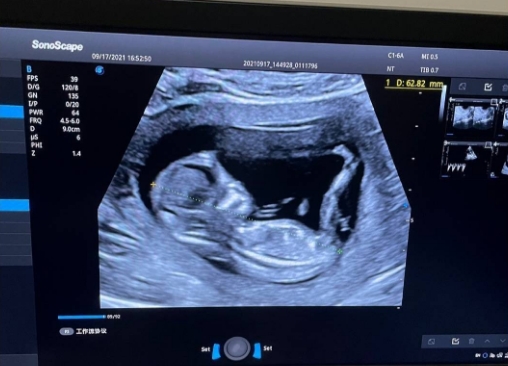

股骨长是B超检查中测量的胎儿大腿骨(从股骨头到股骨远端)的长度,是评估胎儿生长发育尤其是骨骼成熟度的重要依据。它与头围、腹围等指标联合使用,能更精准地判断胎儿是否与孕周相符,排查骨骼发育异常、生长受限等问题。孕24周时,胎儿骨骼进入快速钙化阶段,股骨长的增长速度相对稳定,此时的测量结果对后续孕期监测具有重要参考意义。需要注意的是,股骨长仅反映骨骼发育情况,不能直接等同于胎儿未来的身高,更与胎儿性别无关。

根据临床诊疗指南,孕24周胎儿股骨长的标准值范围为4.38-5.27厘米(即43.8-52.7毫米),平均值约为4.82厘米。临床解读中,更常用“中位数倍数(MoM)”辅助判断,将个体测量值与同孕周胎儿的平均水平对比,24周股骨长MoM值在0.8-1.2之间均属正常。不同医院的检测仪器、测量医生的操作习惯可能导致轻微误差(通常不超过2毫米),因此单次测量的微小偏差无需过度紧张,需结合多次检查的增长趋势综合评估。